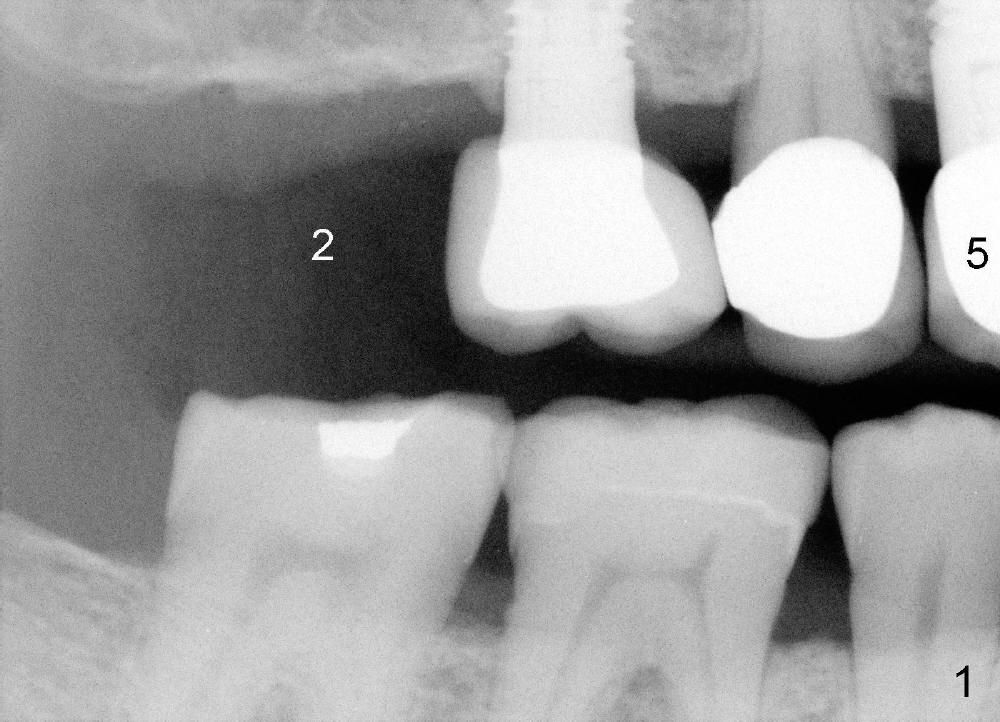

A 71-year-old male is a bruxer. His upper left fixed partial denture was lost 4 years ago (Fig.2). It is replaced by an implant (Fig.3: #14) and two single unit crowns (#13,15). One year later, the tooth #5 is replaced by an immediate implant due to crown fracture (Fig.1,4). Six months after the cementation of #5 implant crown, the tooth #15 is restored by an immediate implant due to root fracture (Fig.6). Recently, porcelain chips off the PFM crown of #13. The patient finally agrees to have another implant (Fig.1: #2) to make his dentition complete and distribute masticatory force more evenly.

The advantage to place implants for a bruxer is that there is sufficient bone height (Fig.2-4). The bone density also appears to be high; there is a thick cortical bone in the edentulous ridge of #2 (Fig.4 arrowheads). Incision will be made; suture may be required for flap fixation. Osteotomy is initiated by 2 mm pilot drill 4 mm from the neighboring tooth (Fig.5); the depth is 8 mm. The depth of the osteotomy is adjusted according to X-ray taken with a parallel pin. Sinus lift may be needed (Fig.5 dashed line: sinus floor). The density of the cancellous bone will be felt and determined while using the 2 mm pilot drill for initial osteotomy. If the density is high, Bicon reamers will be used for further osteotomy and bone saving. Otherwise, osteotomy will be finished mainly with Bone Expander Kit or osteotomes. Bone-level implant is used, followed by a healing abutment. Decortication will be done with a surgical handpiece with a fissure or round bur. If no suture is used for flap fixation, perio glue will be used to close the incision without perio dressing. If the wound is not approximated each other well with sutures, perio glue can be used for complete seal.